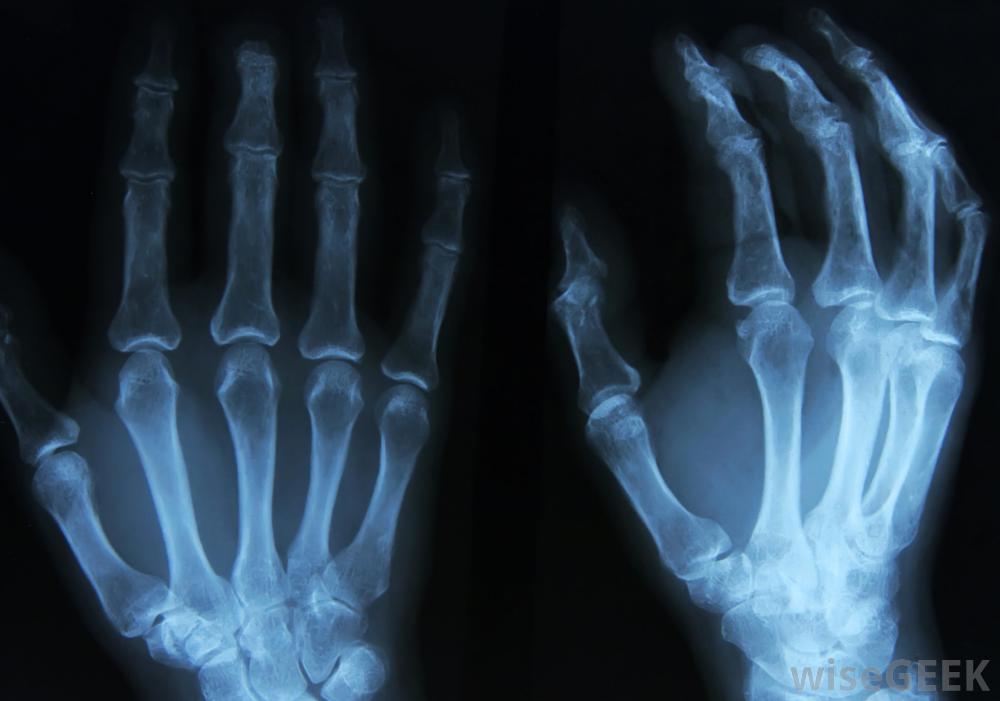

大多数Bouchard和#039;s结节的检查将包括X光片。骨关节炎是不可治愈的,但有一些治疗方法。这种治疗侧重于保持活动性,尽量减少关节变形和处理疼痛。在早期阶段,非处方治疗可能已经足够了,但随着病情的发展,非处方治疗可能不够充分。食物补充或改变饮食也可能是推荐的。Bouchard淋巴结的存在通常可以使早期诊断,并可提示早期反应,使患者能够在不采取更严重措施的情况下控制关节炎。

Bouchard淋巴结是由软骨和骨的突出引起的,称为骨赘,这与骨关节炎的其他症状有关。